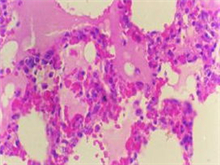

眼睑皮肤丹毒是由乙型链球菌感染引起的皮肤和皮下组织的急性炎症。它主要由面部或其他...